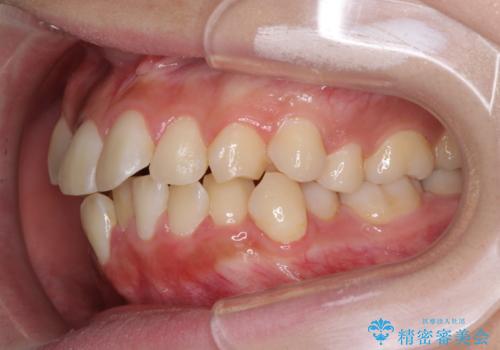

- 八重歯やデコボコをインビザラインで治療したいとのことで来院された患者様です。

インビザライン単体で治療を行うには叢生が強いと判断されたため、事前にワイヤー装置で抜歯矯正を行い、ある程度改善してからインビザラインにて仕上げていくこととしました。